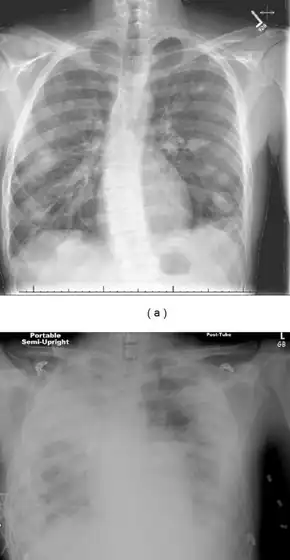

Chest X-ray and chest CT may show pleural effusion, nodules, infiltrates, abscesses and cavitations.